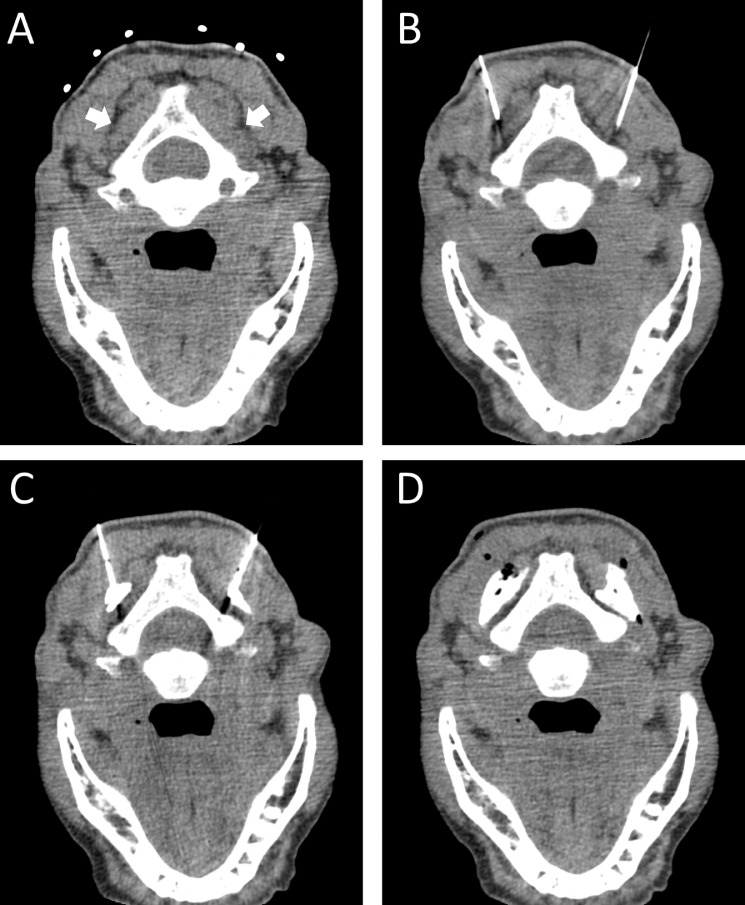

Fig. 2.

Procedural images from CT guided nerve block. (A) Planning axial images at the level of the posterior elements of C2. The target injection sites (white arrows) are the fat planes between the inferior obliqus and semispinalis. (B) Images showing needle placement at the target site followed by (C) images after injection of a small amount of dilute contrast showing infiltration along the fat plane. (D) Post-procedure images showing spread of injectate and contrast along the fat plane